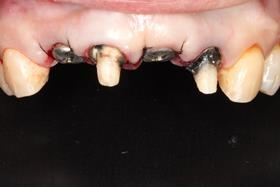

舊牙冠拆除後,右上側門牙及左上正中門牙斷裂。

當天拔牙,且立即植牙。